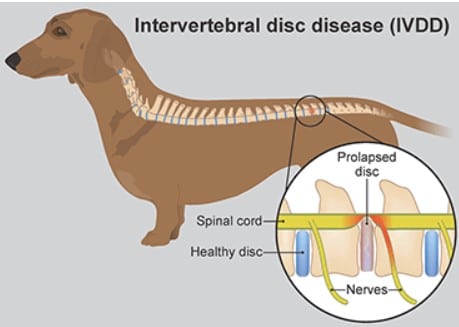

What is a Herniated Disc in Pets?

A herniated disc occurs when an intervertebral disc, or a cushion between vertebrae, cracks or bulges, and the spinal cord gets pinched.

- IVDD (Intervertebral disc disease) in dogs

Why Disc Herniation Is Dangerous

- Compression of the spinal cord reduces the blood flow

- Nerve signals are not transmitted normally

- Without immediate treatment, damage might become irreversible